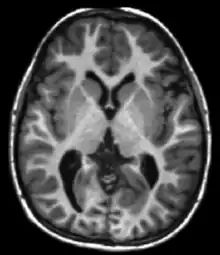

Neuroimaging

MRI is the investigative tool of choice for neurological cancers over CT, as it offers better visualization of the posterior cranial fossa, containing the brainstem and the cerebellum. The contrast provided between grey and white matter makes MRI the best choice for many conditions of the central nervous system, including demyelinating diseases, dementia, cerebrovascular disease, infectious diseases, Alzheimer's disease and epilepsy.[26][27][28] Since many images are taken milliseconds apart, it shows how the brain responds to different stimuli, enabling researchers to study both the functional and structural brain abnormalities in psychological disorders.[29] MRI also is used in guided stereotactic surgery and radiosurgery for treatment of intracranial tumors, arteriovenous malformations, and other surgically treatable conditions using a device known as the N-localizer.[30][31][32] New tools that implement artificial intelligence in healthcare have demonstrated higher image quality and morphometric analysis in neuroimaging with the application of a denoising system.[33]